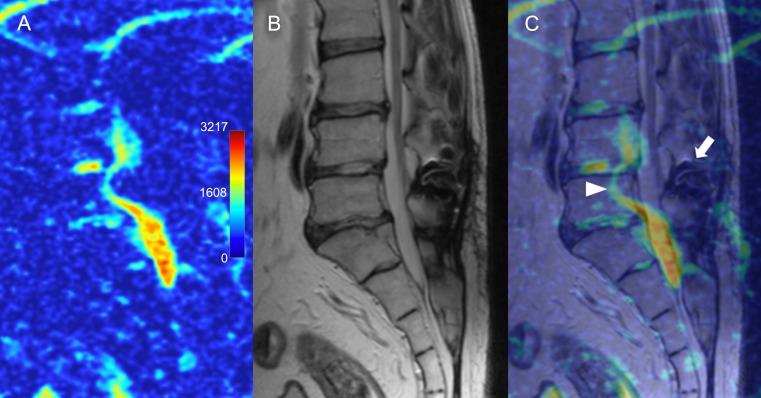

T1-weighted, T2-weighted and diffusion weighted (DWI) MR images of 100 consecutive patients admitted to the spinal surgery service were assessed. ADC maps were generated from DWI images using Osyrix software. The ADC values and characteristic ADC maps were assessed in the regions of interest over the different pathological entities of the lumbar spine.

The study included 452 lumbar vertebral segments available for analysis of ADCs. Characteristic ADC map features were identified for protrusion, extrusion and sequester types of lumbar disk herniations, spondylolisthesis, reactive Modic endplate changes, Pfirrmann grades of IVD degeneration, and compromised spinal nerves. Compromised nerve roots had significantly higher mean ADC values than adjacent (p < 0.001), contralateral (p < 0.001) or adjacent contralateral (p < 0.001) nerve roots. Compared to the normal bone marrow, Modic I changes showed higher ADC values (p = 0.01) and Modic 2 changes showed lower ADC values (p = 0.02) respectively. ADC values correlated with the Pfirrmann grading, however differed from herniated and non-herniated disks of the matched Pfirrmann 3 and 4 grades.

Quantitative and qualitative evaluation of ADC mapping may provide additional useful information regarding the fluid dynamics of the degenerated spine and may complement standard MRI imaging protocol for the comprehensive assessment of surgical patients with lumbar spine pathology. ADC maps were advantageous in differentiating reactive bone marrow changes, and more precise assessment of the disk degeneration state. ADC mapping of compressed nerve roots showed promise but requires further investigation on a larger cohort of patients.